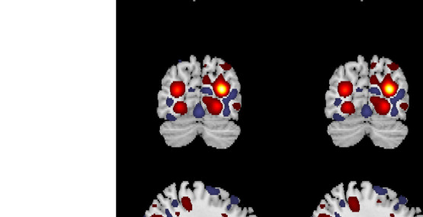

In the last two decades, unsupervised latent variable models---blind source separation (BSS) especially---have enjoyed a strong reputation for the interpretable features they produce. Seldom do these models combine the rich diversity of information available in multiple datasets. Multidatasets, on the other hand, yield joint solutions otherwise unavailable in isolation, with a potential for pivotal insights into complex systems. To take advantage of the complex multidimensional subspace structures that capture underlying modes of shared and unique variability across and within datasets, we present a direct, principled approach to multidataset combination. We design a new method called multidataset independent subspace analysis (MISA) that leverages joint information from multiple heterogeneous datasets in a flexible and synergistic fashion. Methodological innovations exploiting the Kotz distribution for subspace modeling in conjunction with a novel combinatorial optimization for evasion of local minima enable MISA to produce a robust generalization of independent component analysis (ICA), independent vector analysis (IVA), and independent subspace analysis (ISA) in a single unified model. We highlight the utility of MISA for multimodal information fusion, including sample-poor regimes and low signal-to-noise ratio scenarios, promoting novel applications in both unimodal and multimodal brain imaging data.